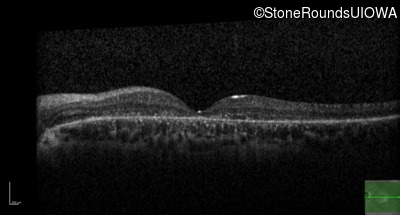

AR Stargardt Disease (IIA)

AR Stargardt Disease (IIA)

| Age at visit: 12 years |

| Age at visit: 13 years |

| Age at visit: 15 years |